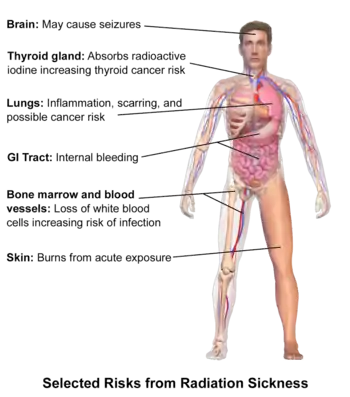

Classically acute radiation syndrome is divided into three main presentations: hematopoietic, gastrointestinal, and neurological/vascular. These syndromes may or may not be preceded by a prodrome.[3] The speed of onset of symptoms is related to radiation exposure, with greater doses resulting in a shorter delay in symptom onset.[3] These presentations presume whole-body exposure and many of them are markers that are not valid if the entire body has not been exposed. Each syndrome requires that the tissue showing the syndrome itself be exposed. [11][7] Some areas affected are:

- Hematopoietic. This syndrome is marked by a drop in the number of blood cells, called aplastic anemia. This may result in infections due to a low number of white blood cells, bleeding due to a lack of platelets, and anemia due to too few red blood cells in the circulation.[3] These changes can be detected by blood tests after receiving a whole-body acute dose as low as 0.3 Gray ,international system of unites, though they might never be felt by the patient if the dose is below 0.7 Gray. Conventional trauma and burns resulting from a bomb blast are complicated by the poor wound healing caused by hematopoietic syndrome, increasing mortality.[1][12][13]

- Gastrointestinal. This syndrome often follows absorbed doses of 6–30 grays (600–3,000 rad).[3] The signs and symptoms of this form of radiation injury include nausea, vomiting, loss of appetite, and abdominal pain.[14] Vomiting in this time-frame is a marker for whole body exposures that are in the fatal range above 4 grays (400 rad). Without exotic treatment such as bone marrow transplant, death with this dose is common.[3]

- Neurovascular. This syndrome typically occurs at absorbed doses greater than 30 grays (3,000 rad), though it may occur at 10 grays (1,000 rad).[3] It presents with neurological symptoms such as dizziness, headache, or decreased level of consciousness, occurring within minutes to a few hours, and with an absence of vomiting. It is invariably fatal.[3]

Early symptoms of ARS typically includes nausea and vomiting, headaches, fatigue, fever, and a short period of skin reddening.[3] These symptoms may occur at radiation doses as low as 0.35 grays (35 rad). These symptoms are common to many illnesses, and may not, by themselves, indicate acute radiation sickness.[3]